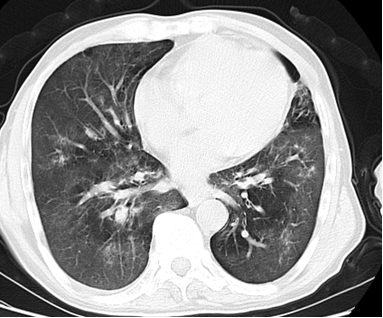

我院多学科协作成功诊断一例疑难病:卡氏肺孢子菌病

近日,我院多学科协作团队成功诊断一例卡氏肺孢子菌病(PCP)。

据了解,肺孢子菌病是由卡氏肺孢子菌所引起的呼吸系统机会感染。卡氏肺孢子菌体寄生在肺泡内,其临床特征:发热、干咳、呼吸急促、呼吸困难和发绀等,症状呈进行性加剧,病死率高。   该病发病无性别和季节差异。得注意的是在不同个体及疾病的不同病程,PCP临床表现差异甚大。

据呼吸与危重症医学科主任温永权介绍,该病主要的感染途径为空气传播和体内潜伏状态PC的激活。PC在肺内繁殖并逐渐充满整个肺泡腔,并引起肺泡上皮细胞空泡化,脱落。其潜伏期一般为2到4周。需要较高的诊断能力才能明确诊断。

患者影像学表现

(上图为检查结果)